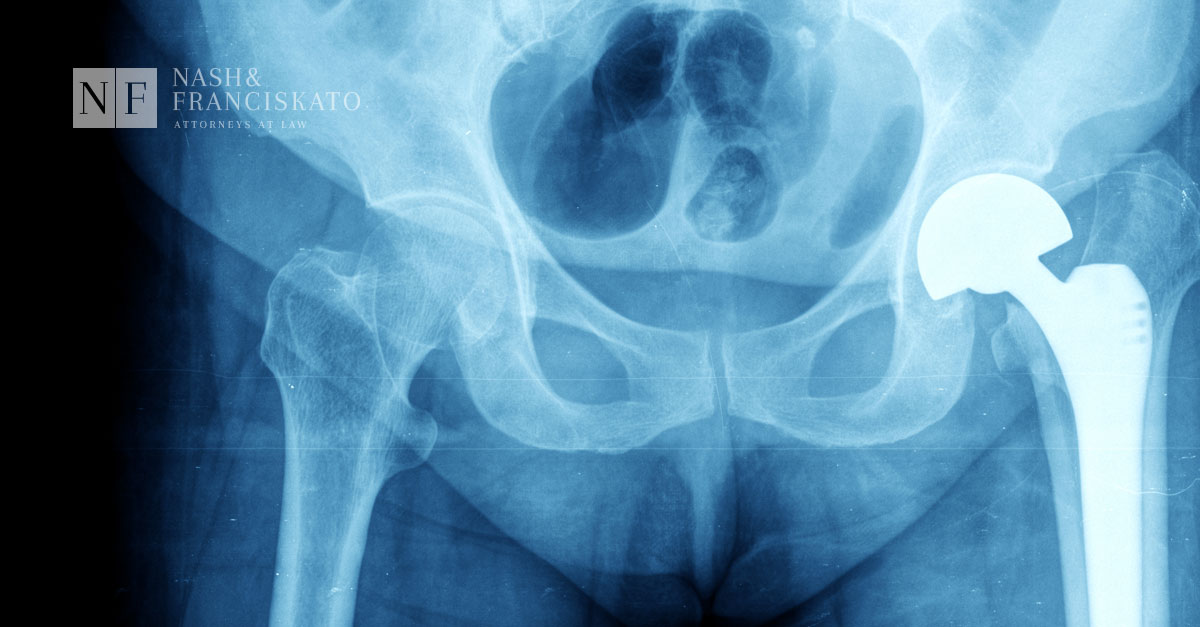

What is a Hip Replacement?

More and more people turn to hip replacement surgeries to give them back their mobility and to relieve the pain caused by diseases such as osteoarthritis.

Record $1 Billion Verdict in Pinnacle Hip Replacement Trial

Yesterday, a federal jury in Dallas, TX, awarded a record $1 billion verdict against Johnson & Johnson and its DePuy Orthopaedics unit to six plaintiffs injured by the company’s Pinnacle metal-on-metal hip implants.

Wright Medical: $240 Million Metal-on-Metal Hip Settlement

On November 1, 2016, under a Master Settlement Agreement (MSA), Wright Medical Technology, Inc., reached a $240 million settlement agreement for nearly 1,300 product liability lawsuits filed by individuals nationwide over its metal-on-metal hip implants.